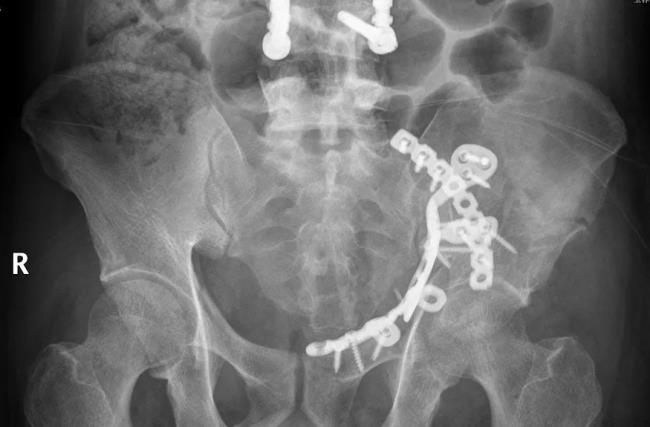

此图为患者术后影像资料

在完善各项术前准备后,骨盆科医疗团队在于2021年6月9日在插管全麻下对覃先生行左髋臼骨折切开复位内固定术。手术时间仅花费2小时,手术切口仅8厘米,术程非常顺利。

鉴于髋臼骨折的特殊性,针对覃先生的病例,骨盆科利用3D打印模型高度还原患者骨折状态,从模型上可以清晰的看到患者左髋部多处粉碎性骨折,并且整个髋关节中心已经严重脱位,像这样复杂的髋臼骨折该如何处理才能又好又美观呢?经过骨盆科医疗团队多次和患者家属进行耐心沟通及讲解,患者家属最终决定采用医生的建议,摒弃传统的髋臼骨折内固定钢板,使用更为精简、高效的髋臼翼型一体化钢板进行固定。一体成型的钢板,将骶髂关节下方、前柱、后柱整体固定,符合力学传导,预防后期松动,骨折复位钢板贴合效果也更加满意,后期康复速度也会有所增加。